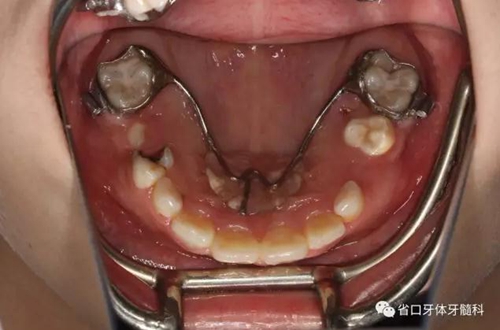

口內(nèi)情況:牙合 面觀

檢查:替牙列,12、21已萌出,11、22未萌,12、21間隙約5mm,右上前牙區(qū)前庭溝處見黏膜隆起,11牙冠未破齦。